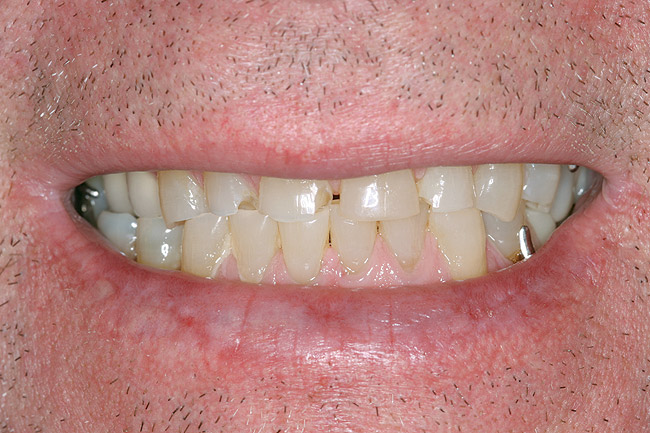

Figure 18  Under-reduction of the incisal third created an error of position to the facial. Because of the lip dynamics of this patient, comfort was not achieved. The patient always felt aware of her teeth. Retreatment was needed.

Figure 18

Figure 19 through Figure 21 The new restorations of the patient seen in Figure 18. The incisors now have a convex profile and lingualized incisal edge. Lip and phonetic comfort were normalized.

Figure 19

Figure 20

Figure 21